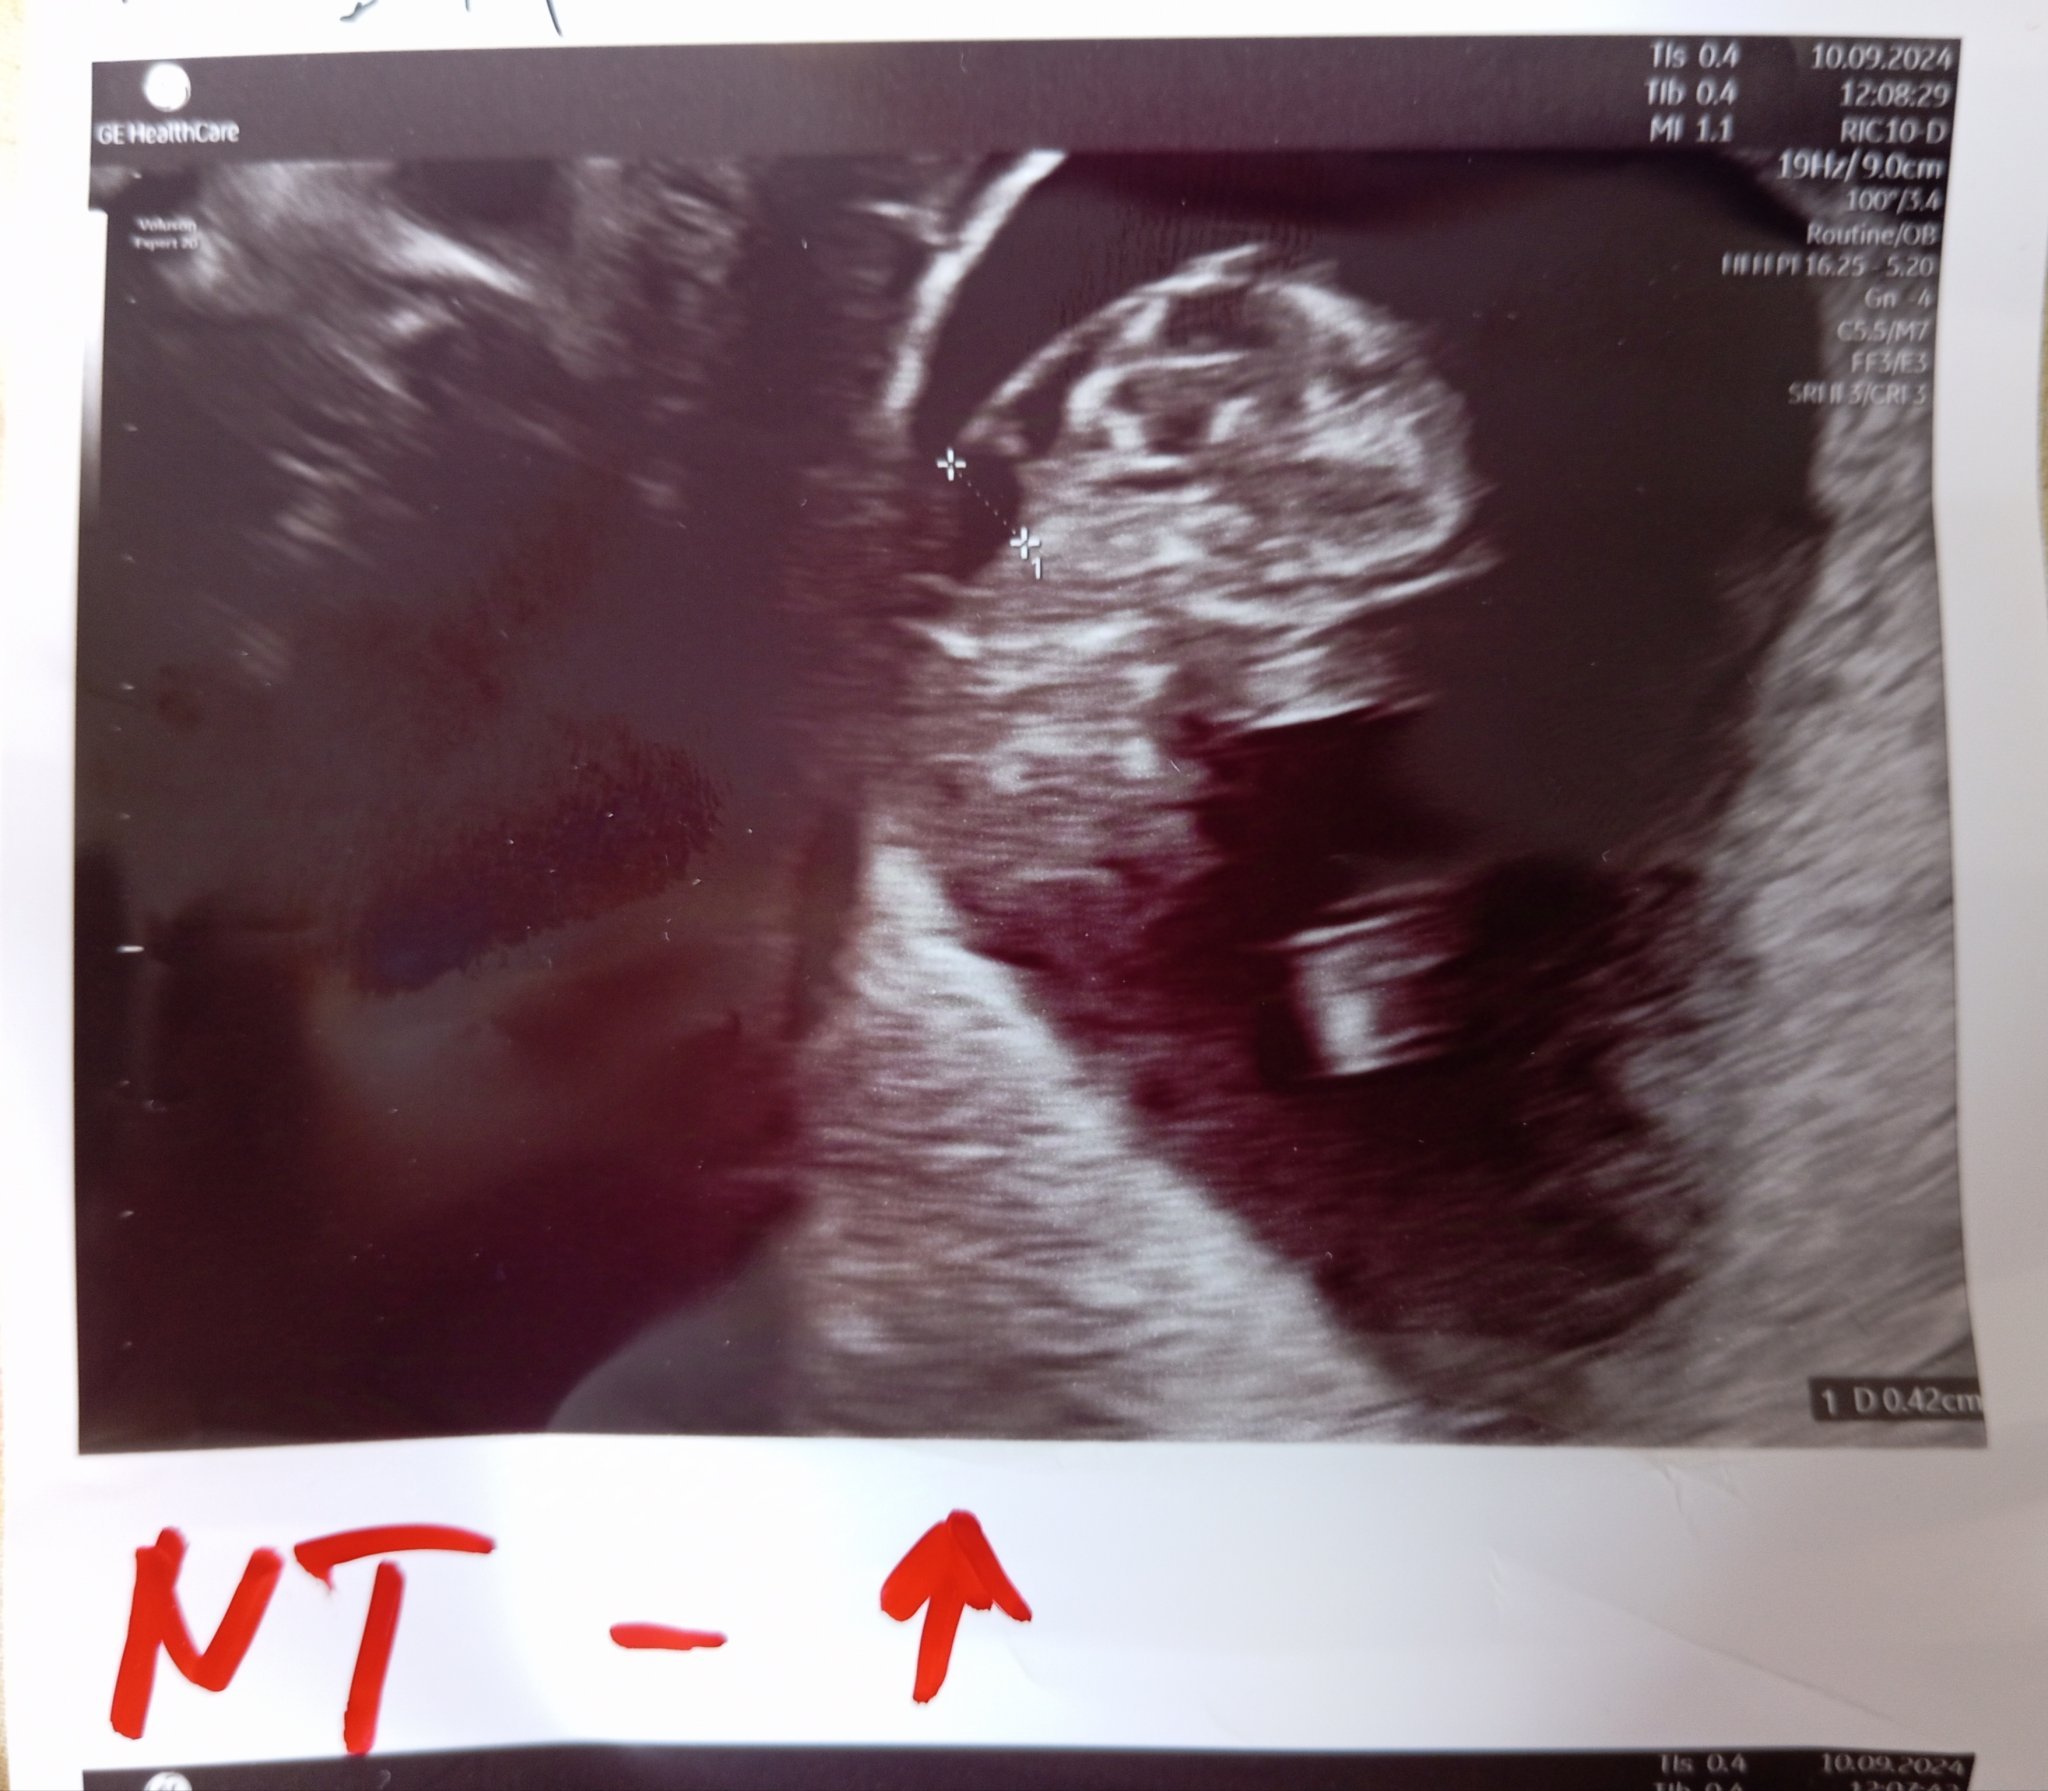

Какво представлява NT и какви са нормалните стойности?

NT (neck thickness или гъвкавост на врата) е ултразвуков показател, който се измерва за оценка на риска от хромозомни аномалии. Нормалните стойности за NT са под 3 мм, но за точна интерпретация е необходимо да се разглеждат и други маркери. Стойности над 3,5 мм увеличават риска и могат да наложат допълнителни изследвания.